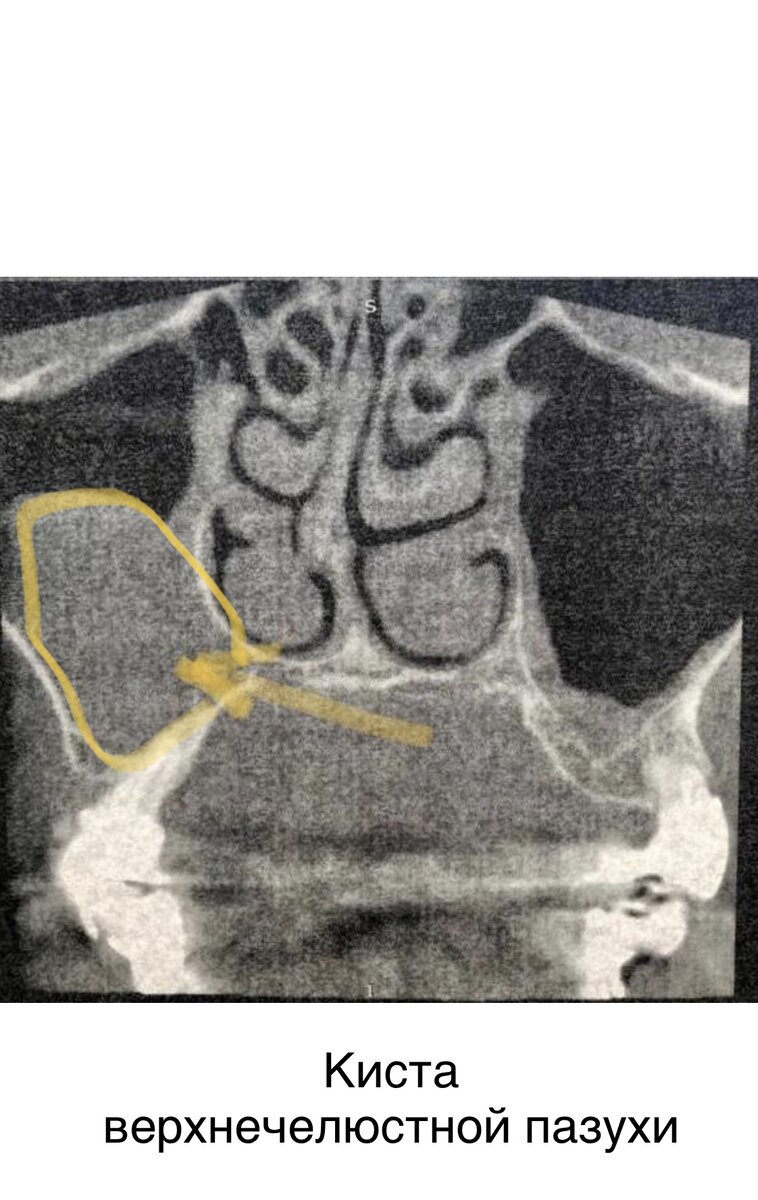

При обследовании установлен диагноз: Хронический правосторонний верхнечелюстной синусит. Киста правой верхнечелюстной пазухи. Постравматическая деформация и атрофия альвеолярного отростка верхней челюсти

⠀ ☑️Проведена операция: Риноантростомия справа с удалением кисты. Винирная пластика альвелярного отростка верхней челюсти костным аутоблоком с ветви нижней челюсти. ⠀ Киста удалена эндоназально без наружных разрезов. В ходе операции использовался пьезохирургический модуль для забора аутокостных блоков, для закрытия костного дефекта на месте отсутствующих зубов. ⠀